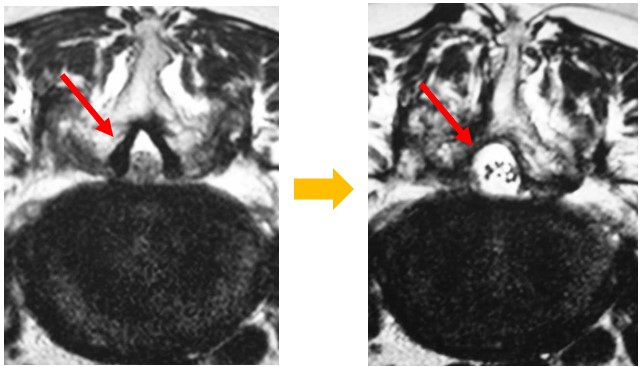

MELの術前・術後のMRI画像

MELはMEDを応用したもので、神経を圧迫している骨や靭帯などを切除して脊柱管をくりぬくように切除します。複数個所(椎間)の手術も可能です。1椎間の平均的な手術時間は40~50分程度です。